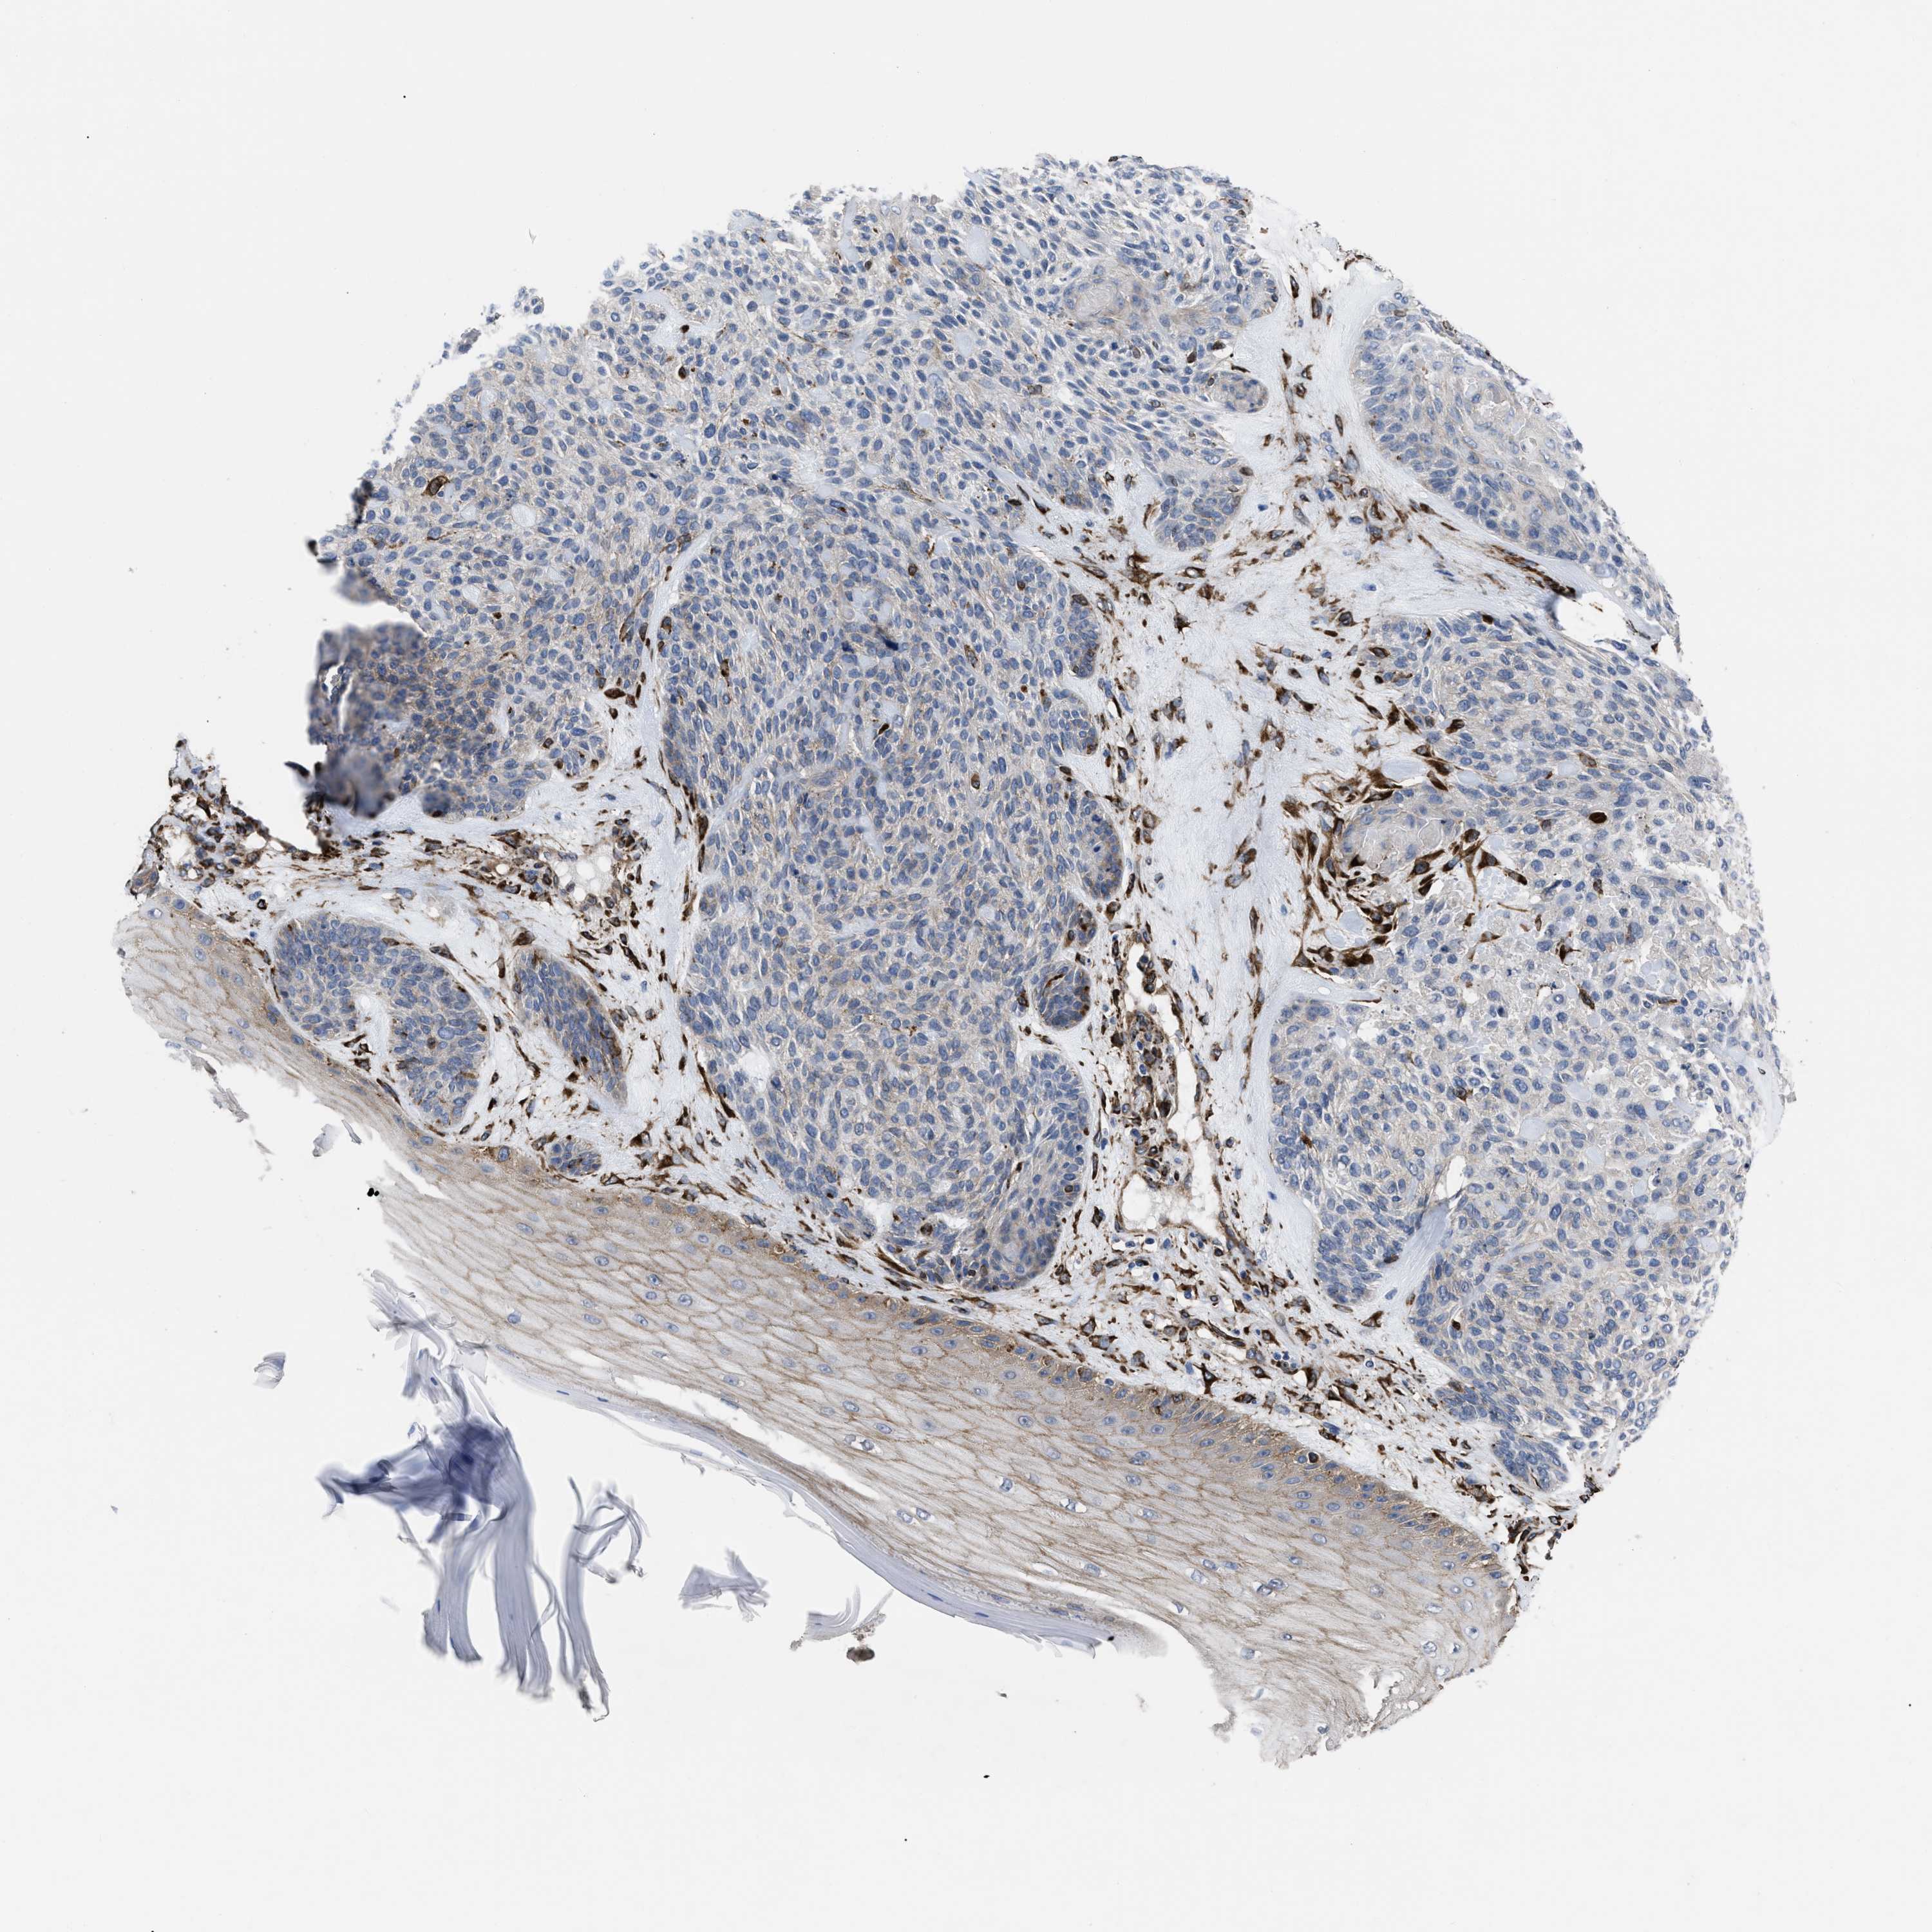

SKIN CANCER - Protein expressioni

A mouse-over function shows sample information and annotation data. Click on an image to view it in a full screen mode. Samples can be filtered based on level of antibody staining by selecting one or several of the following categories: high, medium, low and not detected. The assay and annotation is described here.

Each image is clickable and will lead to virtual microscopy that enables deeper exploration of all samples and also displays staining intensity scores, fraction scores and subcellular localization as well as patient and tissue information for each sample.

Antibody HPA020762

Staining

High

Medium

Low

Not detected

Intensity

Strong

Moderate

Weak

Negative

Quantity

>75%

75%-25%

<25%

None

Location

Nuclear

Cytoplasmic/membranous

Cytoplasmic/membranous,nuclear

Squamous cell carcinoma in situ, NOS

Squamous cell carcinoma, NOS

Squamous cell carcinoma, metastatic, NOS

Basal cell carcinoma